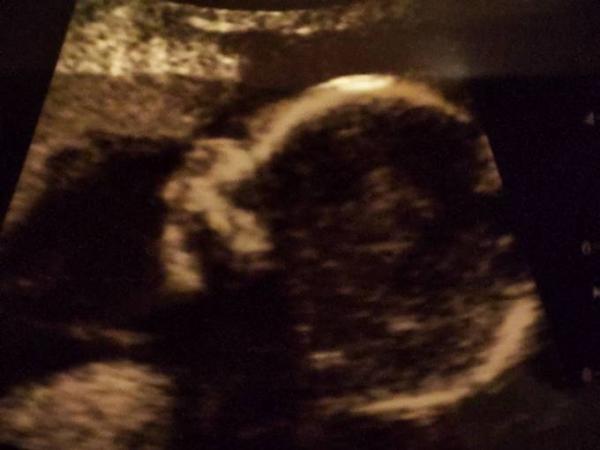

Zweite VU nach langen 7 Wochen.

Heute 18+2. Alle Werte sind super.

Größe etwa 17/18 cm und 245 g.

Wir haben kein Outing weil es mit dem Rücken nach vorne lag, selbst ein Profilbild war sehr schwierig zu ergattern, aber es gibt eine Tendenz.

Am 11.11. haben wir das Organscreening, da sieht man es hoffentlich besser.